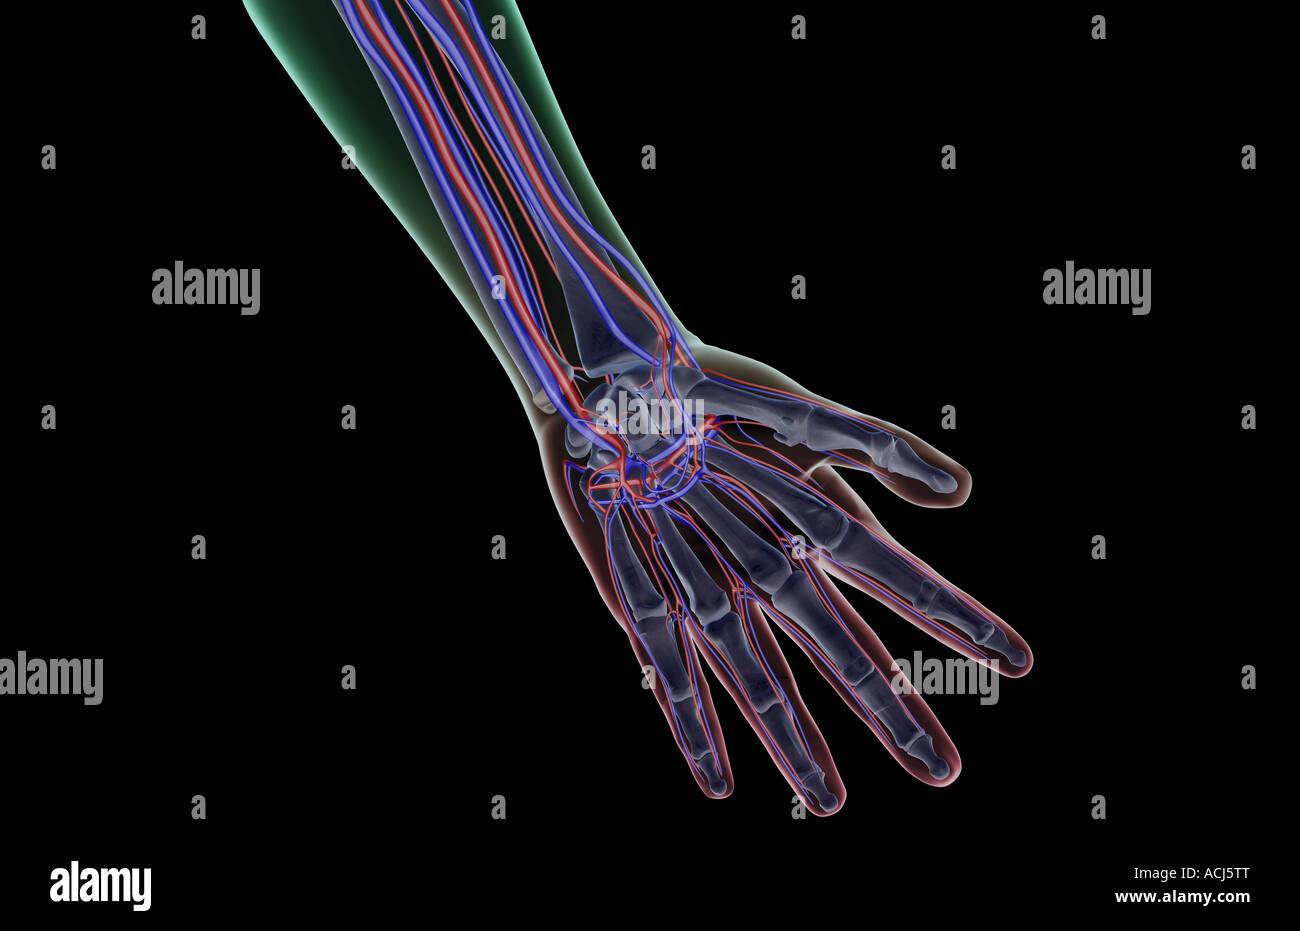

The blood supply of the hand Stock Photohttps://www.alamy.com/image-license-details/?v=1https://www.alamy.com/stock-photo-the-blood-supply-of-the-hand-13166903.html

The blood supply of the hand Stock Photohttps://www.alamy.com/image-license-details/?v=1https://www.alamy.com/stock-photo-the-blood-supply-of-the-hand-13166903.htmlRFACJ5TT–The blood supply of the hand